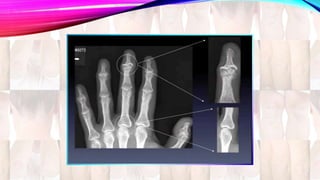

• Early diagnosisof psoriatic arthritis is important, as disease progression often results in loss of function. • There are no specific serologic tests for establishing the diagnosis of psoriatic arthritis. • X-Ray: Enthesitis (inflammation of the insertion points of tendons and joints into bone).Periosteal new bone formation.

• 69.

•The blue arrow= a normal joint space. • Red arrow = “cup and saucer” effect of the fourth metatarsal bone being jammed into the base of the fourth toe. •The yellow circle = “Pencil appearance” destruction characteristic of the disease.